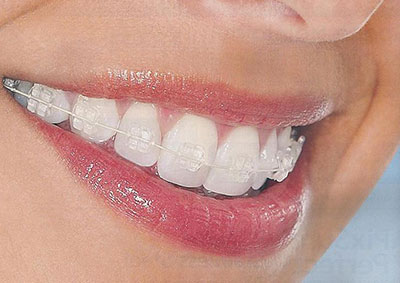

Os braquetes cerâmicos – estéticos – são muito aceito pelos pacientes, pela capacidade de mascarar a aparência do aparelho fixo, tornando-se quase invisíveis ao olhar. Assim, se você se preocupa com a aparência do seu sorriso, os braquetes estéticos são uma ótima opção.